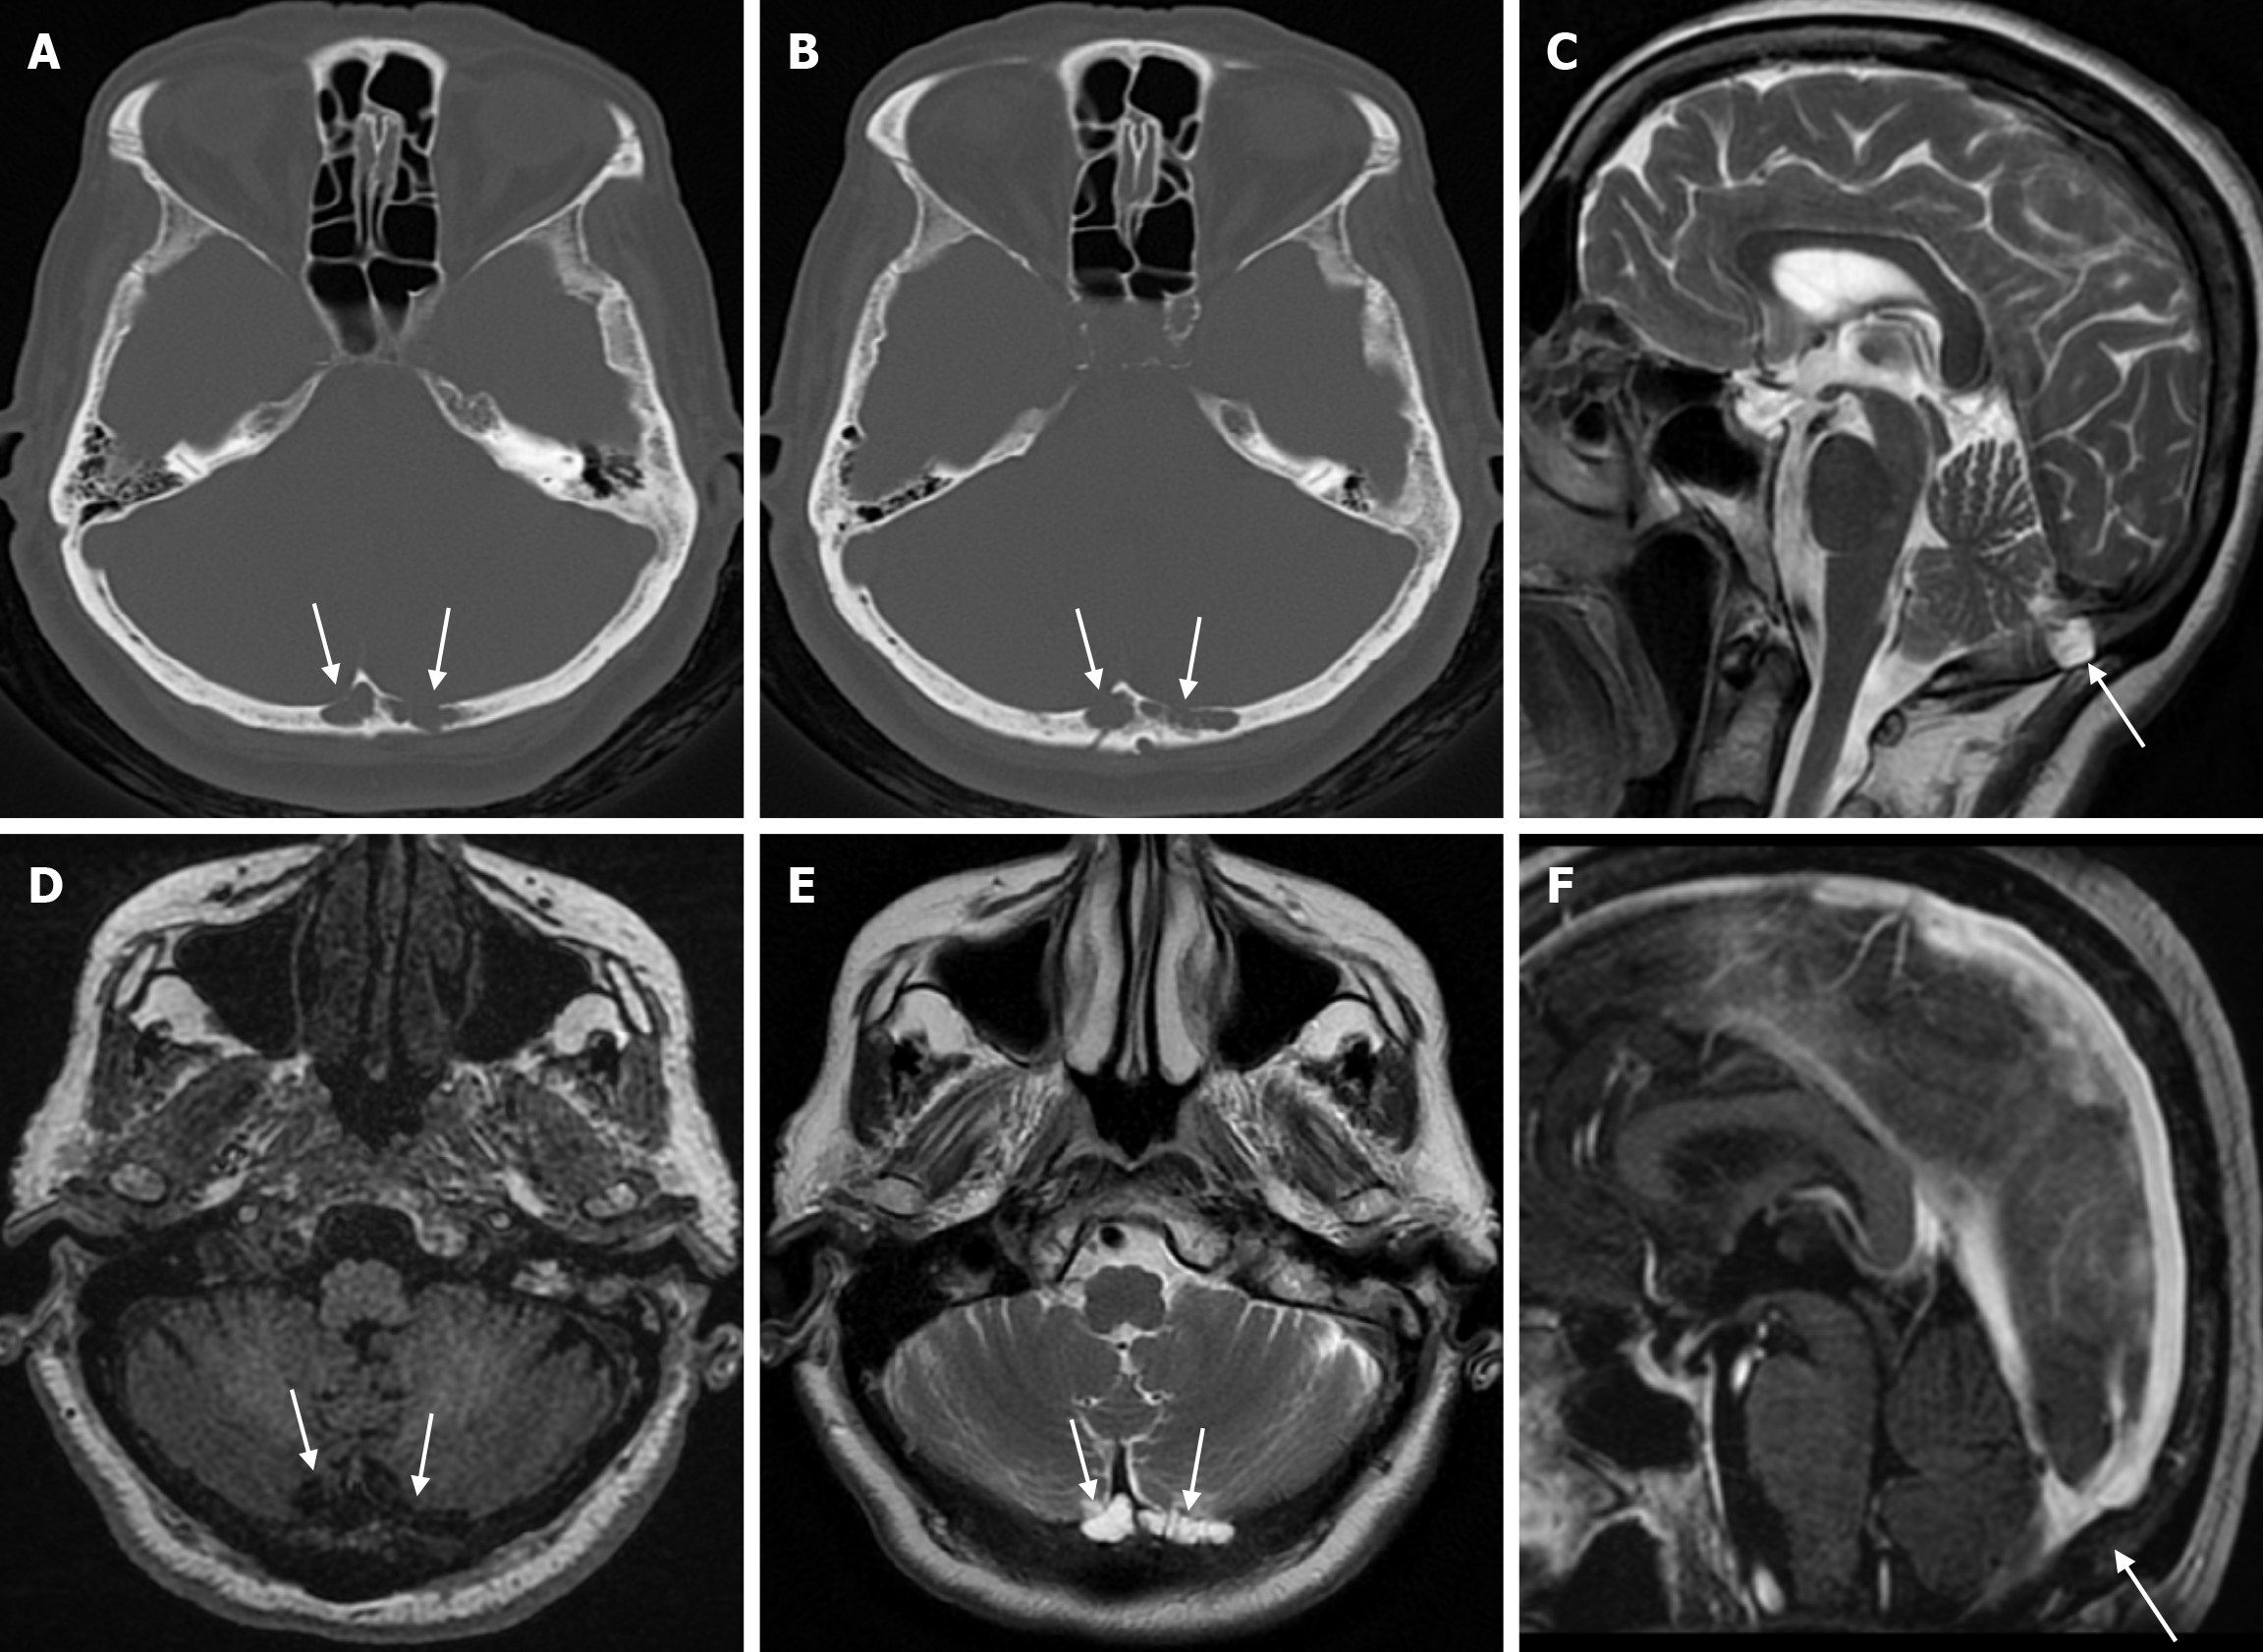

Arachnoid granulations (Pacchionian granulations) are cerebrospinal fluid-filled projections that extend from the subarachnoid space through openings in the dura into the venous sinuses and can be seen macroscopically. Their incidence varies from 0.3% to 55%. Arachnoid granulations are usually seen in millimeter dimensions, but may grow to fill the dural sinuses or arch the inner table[11]. In addition, intraosseous arachnoid granulations can sometimes extend to the inner table of the bone, causing scalloping, remodeling or bone erosion of the inner table[12]. The prevalence of arachnoid granulations increases with age, but there is no difference in gender distribution. Arachnoid granulations with a slight left hemispheric predominance are found in the dural venous sinuses, most frequently in the transverse sinuses and especially in the middle or lateral parts. The second most common location is the superior sagittal sinus, but they can be found anywhere in the dural venous sinuses. Arachnoid granulations are usually detected incidentally. If they fill and expand the dural sinuses, causing partial sinus obstruction, they may cause symptoms of increased intracranial pressure due to venous hypertension. They are usually associated with headaches. Arachnoid granulations may be seen as radiolucent areas on plain radiography of the skull or may cause compression on the inner table of the skull. On CT imaging, arachnoid granulations can be seen as sharply demarcated, hypodense structures in close relation to the dural venous sinus. On MRI, they usually show hyperintense signal on T2-weighted images and hypointense or isointense signal on T1-weighted images compared to brain parenchyma (Figure 1). On CT angiography, MR angiography or catheter angiography imaging, arachnoid granulations appear as oval or round filling defects in the dural venous sinuses during the venous phase[11]. Recent advances in radiology have made it possible to identify brain herniations into the arachnoid granulation by improving image quality with higher resolution and thinner slice three-dimensional T1-weighted and T2-weighted MRI sequences (Figure 2). Brain herniation into the arachnoid granulation is rare in the literature, and the incidence of brain herniation into the calvarial or dural sinuses has been reported to be 0.32%[13]. Arachnoid granulations may be confused with pathological processes in the dural venous sinuses[11]. In the differential diagnosis of arachnoid granulations, venous sinus thrombosis, dural-based tumors, or structures such as septa and fat that may cause filling defects in the dural venous sinuses should be considered[12]. Dural sinus thrombosis usually fills an entire sinus segment or several sinuses and may extend to the cortical veins, whereas arachnoid granulations appear as focal and well-defined defects. Fresh thrombus in the dural sinuses are hyperdense on CT and hyperintense on T1-weighted MRI. Differential tumor diagnosis can be made based on its shape, lack of contrast enhancement and diffusion restriction[11].

The transcalvarial venous channels are the openings in the calvarium that connect the dural venous sinuses to the extracranial veins via emissary veins. They are usually seen as serpentine or linear lucencies with sclerotic margins along the skull, and when these vessels are dilated they are known as venous lakes. Venous lakes are sometimes confused with fractures or sutures[14]. Venous lakes are present in about 15% of patients and are not associated with age or gender[15]. Venous lakes appear on CT as round or oval lucencies at the level of the skull base (Figure 3). On MRI, they show medium or low signal intensity on T1-weighted images, high signal on T2-weighted images, and significant contrast enhancement is seen in contrast-enhanced series[14]. It is important to distinguish venous structures from metastases. Metastases often show restricted diffusion within the lesion due to high cellularity. In addition, metastases may show increased blood flow within the lesion. Metastases often invade adjacent tissues[15].

Small parietal foramina (approximately 1-2 mm in diameter) are intramembranous bone development defects that occur in 60% to 70% of the population. The parietal foramina close during the fifth month of normal embryonic development and give rise to emissary veins that anastomose with the superior sagittal sinuses. Enlarged parietal foramina (> 5 mm) occur at a rate of 1:15000 to 1:50000. These parietal/biparietal foramina arise as a result of abnormal calvarial ossification around the parietal notch during fetal development. At birth there is a large single midline or bilateral calvarial defect with the brain covered by the dura, pericranium and overlying scalp. Individuals with enlarged parietal foramina present with symptoms of severe headache, vomiting and intense pain when mild pressure is applied to the unprotected cerebral cortex. Parietal foramina may rarely be seen together with craniofacial and skeletal anomalies, myelomeningocele, and encephalocele. Genetic studies have shown a familial occurrence with autosomal dominant inheritance. Mutations in the MSX2 and ALX4 genes have been reported in almost 80% of parietal foramina cases[16]. CT scan shows single or double rounded defects in the parietal bone adjacent to the intersection of the sagittal and lambdoid sutures. The defects may be large and confluent along the midline. MRI is the preferred method to detect venous, cortical or meningeal abnormalities associated with the parietal foramina[14].

The beaten copper skull shows prominent convolutional markings on several bones of the skull. These convolutional markings normally appear between the ages of 2-3 and 5-7 years, which are periods of rapid brain growth. The occurrence of convolutional markings in children younger than 18 months should suggest a cause leading to increased intracranial pressure due to processes such as obstructive hydrocephalus, craniosynostosis or intracranial masses. Beaten copper skull pattern develops because of pressure applied to the soft skull by the growing brain. The beaten copper skull is usually confined to the posterior part of the inner table of the skull, but this appearance can affect the entire skull. Plain radiography of the skull can be an important diagnostic tool to detect increased intracranial pressure. In children, CT and three-dimensional reconstructions are best used to evaluate the convolutional markings (Figure 5) and cerebral ridges for surgical planning[23].

Atretic encephalocele is a midline scalp mass covered by skin containing meninges and neural remnants and/or degenerated brain tissue. In atretic encephaloceles, the brain tissue in the scalp degenerates and may remain attached to the dura mater by a fibrous stalk intracranially. Atretic cephaloceles may be associated with a persistent falcine vein characterized by a vertical embryonic position of the straight sinüs (Figure 6). Most atretic encephaloceles are parietal in location. On CT imaging, a subgaleal soft tissue mass may be seen in a “spinning top” configuration. CT imaging helps visualize bone defects, while MRI helps determine the contents of the encephalocele[3]. The lesions most commonly confused with atretic encephaloceles are sinus pericranii and dermoid cysts[25].